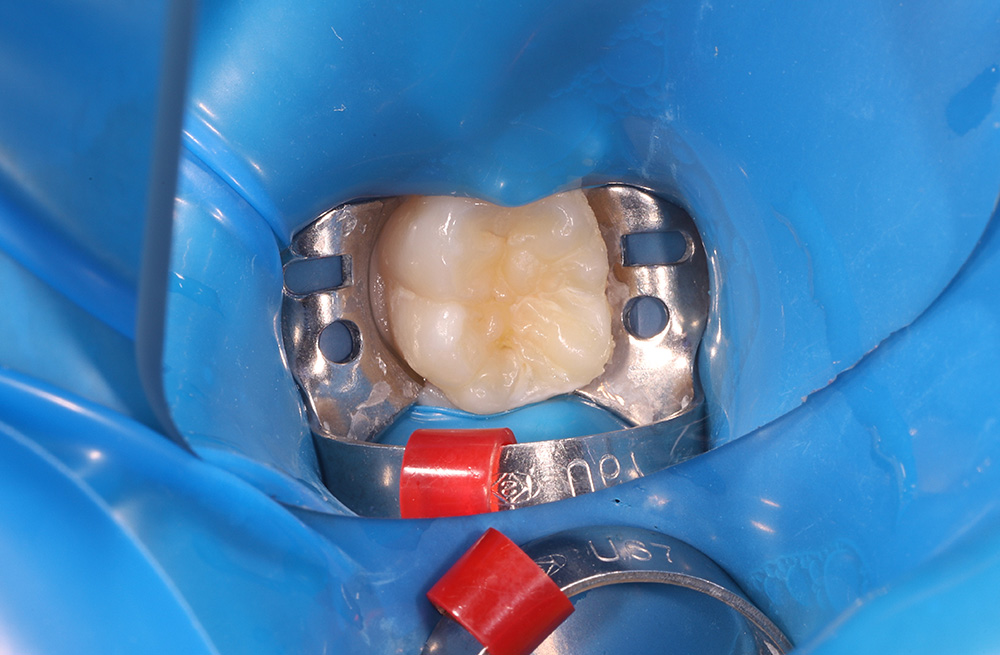

Лечение кариеса на жевательной поверхности постоянного зуба у подростка